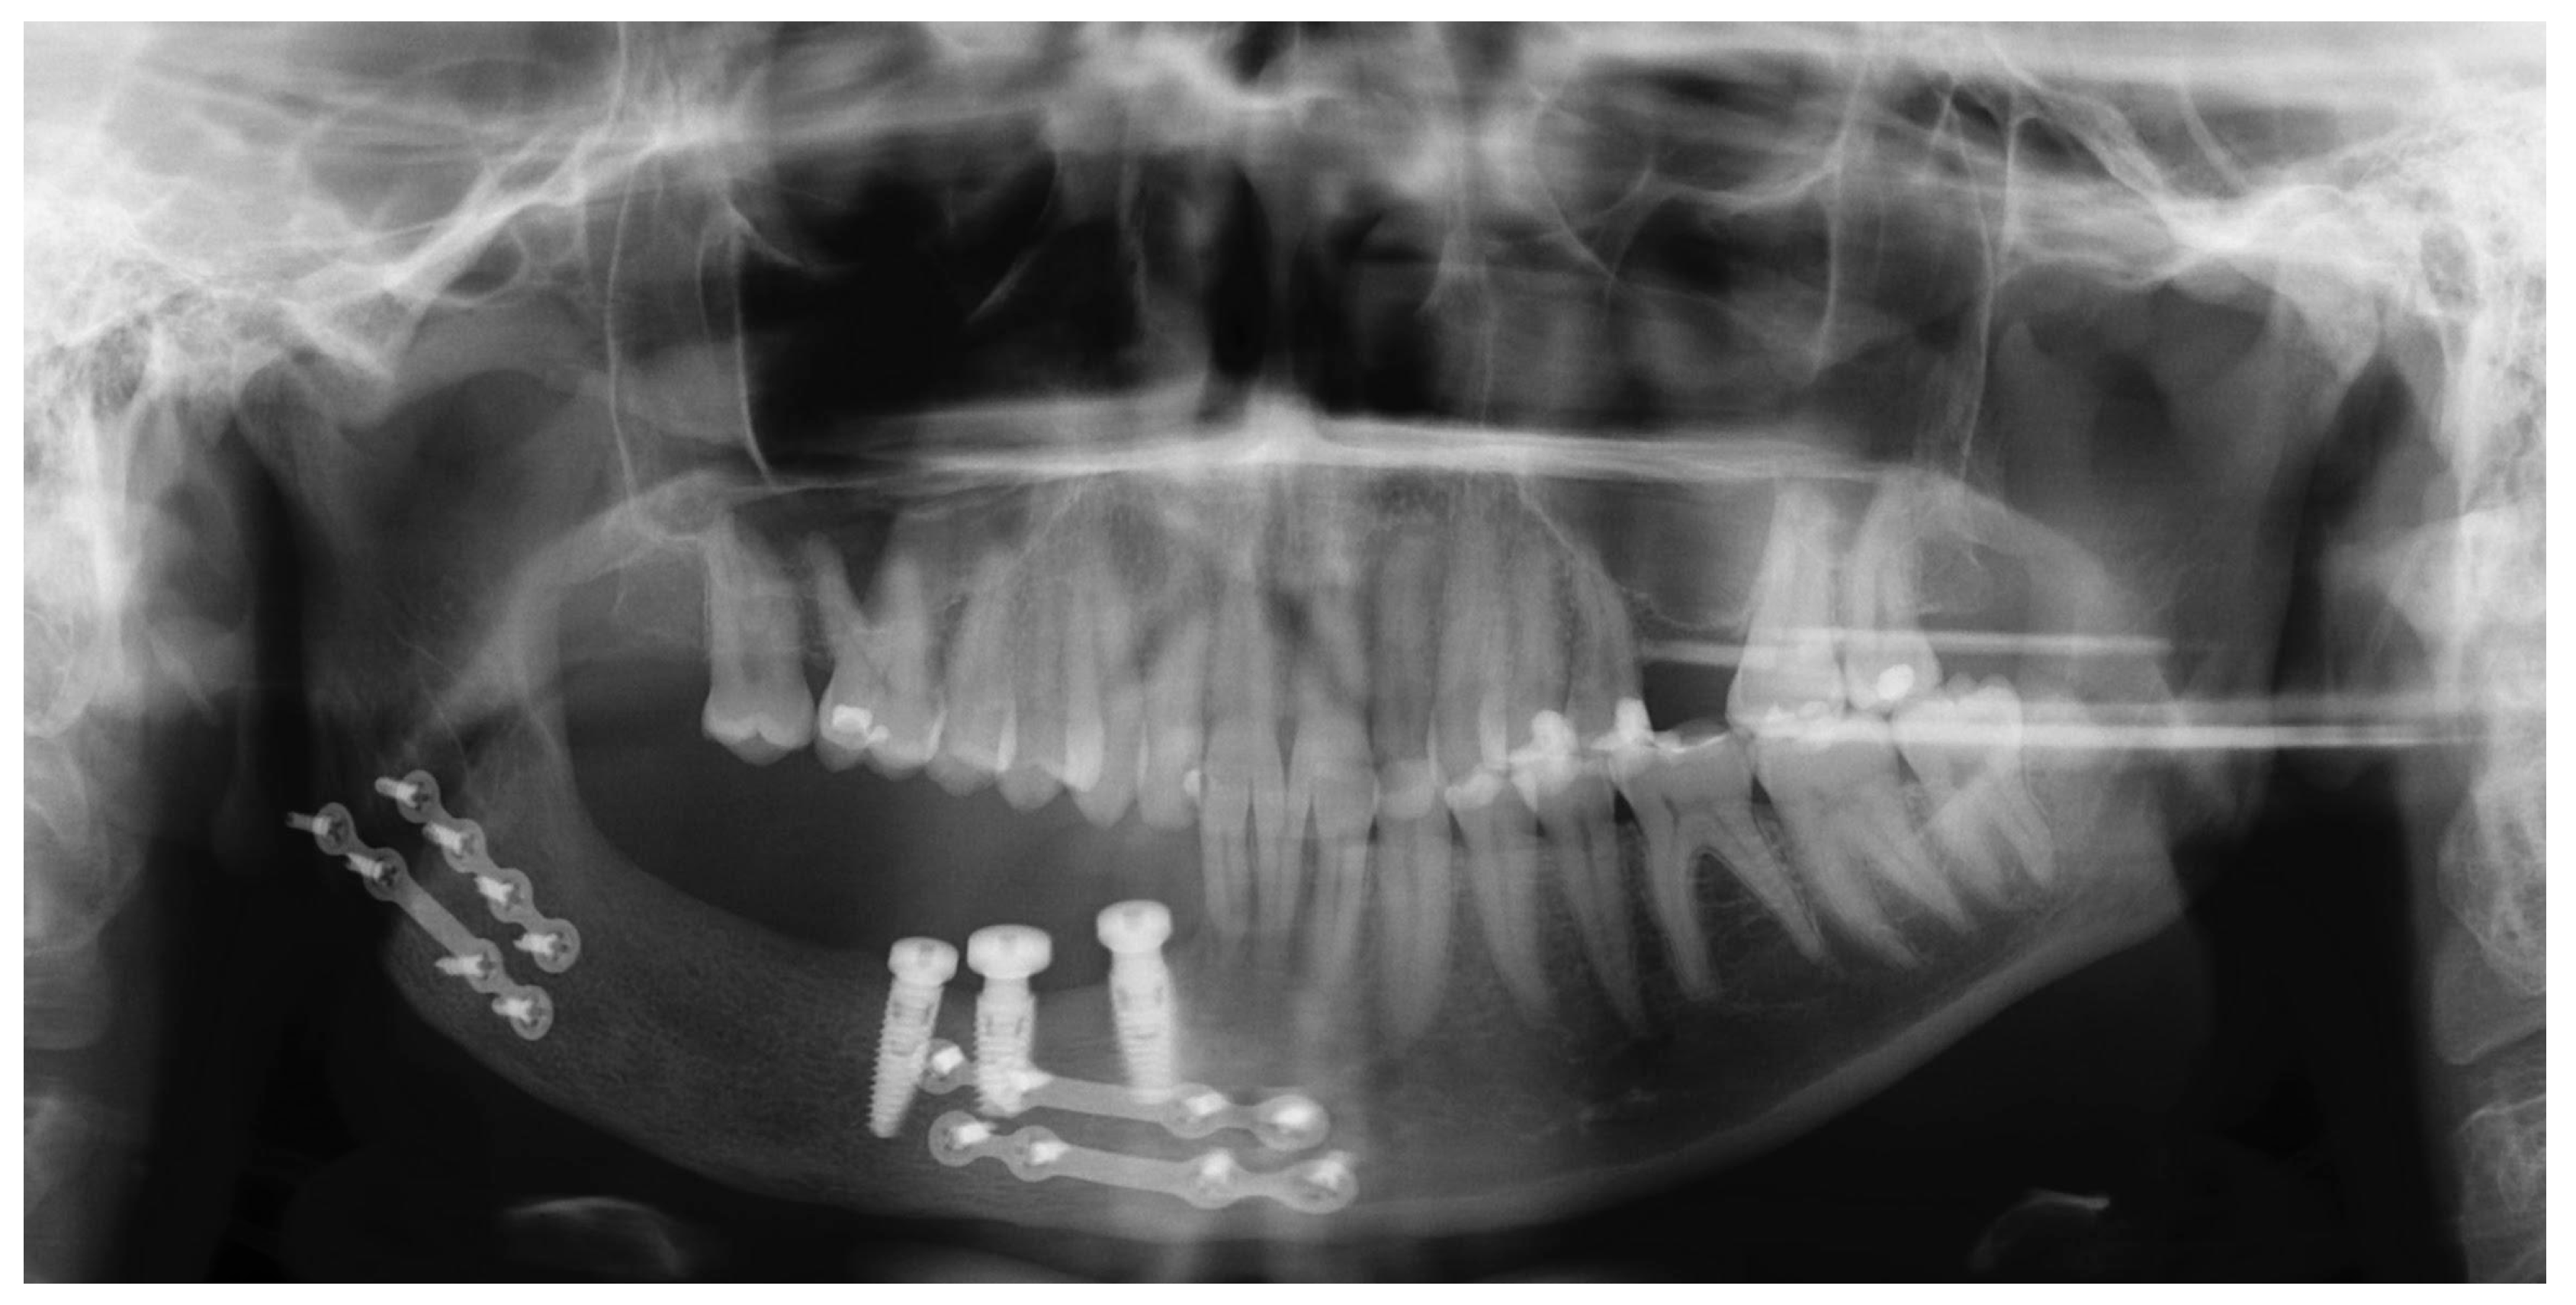

2.2. Treatment Procedures and Histopathological Results

2.3. Postoperative Care

2.4. Follow-Ups